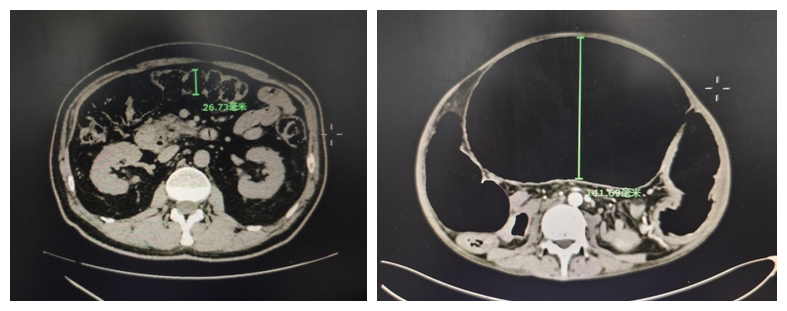

正常的结肠(左图)与此名患者病变的巨结肠(右图)对比